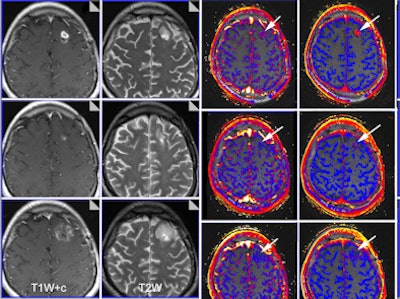

| Functional imaging biomarkers can provide important clinical information. In this case, multiparametric MRI was used to evaluate brain glioma response to bevacizumab therapy. Columns: T1-weighted images with contrast; T2-weighted images; transfer constant and leakage space. Rows (from the top): baseline, 10 days of therapy, and six weeks of therapy. Note that morphology imaging shows an initial response by the 10th day, but the tumor then progresses and is much larger at six weeks. However, functional images show that the drug is still working (reductions of transfer constant and leakage space - arrows). Images courtesy of Dr. Anwar Padhani, Paul Strickland Scanner Centre, Mount Vernon Cancer Centre, London, who was a co-author of the RSNA 2012 e-poster. The images have been published in part in the following article: Padhani AR, Miles KA. Multiparametric imaging of tumor response to therapy. Radiology. 2010; Vol. 256:2, pp. 348-364. |

BMs are necessary because morphologic imaging does not always allow us to predict who will respond, or who is responding, to therapy. Also, key biological tumor hallmarks are not evaluated using conventional imaging techniques, and tumor size is a late and inaccurate measurement for tumor response and nonmeasurable disease (i.e., peritoneal and bone) may represent the most important portion of tumor burden. Size change does not necessarily reflect therapeutic efficiency, and new therapies are often cytostatic and may not change tumor size, they added.